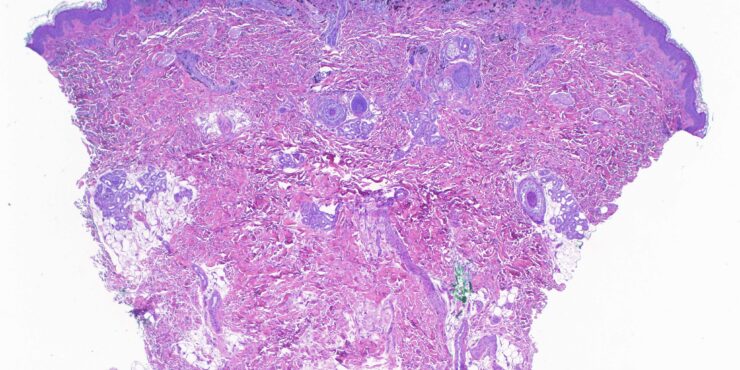

Read MoreSpir adenocylindroma = الاسطوانوم الغدي العرقي

Read MoreSpiradenoma=ورم غدي عرقي OLYMPUS DIGITAL CAMERA OLYMPUS DIGITAL CAMERA OLYMPUS DIGITAL CAMERA OLYMPUS DIGITAL CAMERA OLYMPUS DIGITAL CAMERA